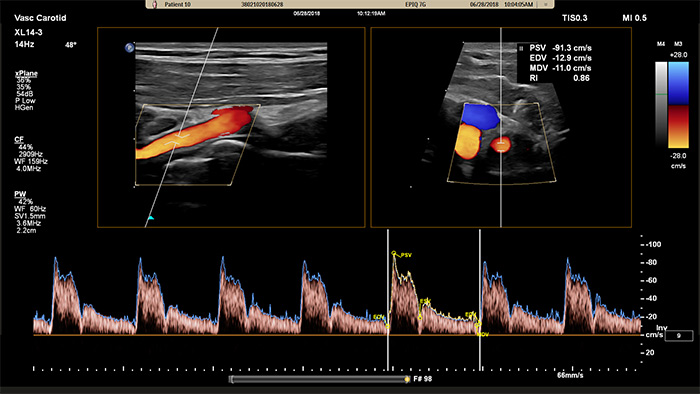

Il trasduttore XL14-3 xMatrix offre inoltre funzionalità Doppler xPlane. Il Doppler a onda pulsata (PW) xPlane consente un posizionamento preciso del volume del campione Doppler utilizzando contemporaneamente le immagini di riferimento longitudinale e trasversale. Vantaggio principale: il Doppler xPlane riduce gli errori di posizionamento del volume del campione e fornisce maggiore riproducibilità e coerenza durante il campionamento di stenosi significative.